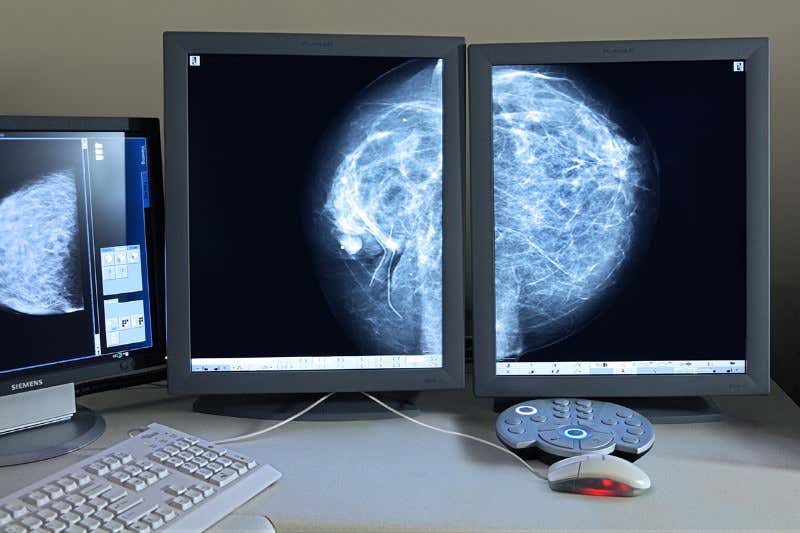

During puberty the mammary gland forms a network of milk-ducts that are repeatedly reshaped through a woman’s life to allow her to provide milk for any children she may have. But the regenerative processes that enable this to happen are poorly understood. Unravelling them could help us better tackle breast cancer as it is the cells of this mammary gland network that usually go awry.

Christina Scheel at the Helmholtz Centre for Health and Environmental Research in Munich and her team took mammary gland cells from donated human tissue and added them to gels made of collagen fibres, a common type of connective tissue. The cells spread out and connected to these fibres, pulling on them. This generated a physical force that enabled the cells to grow into a new mammary gland network inside the Petri dish.

“We want to model breast cancer using our tool, and test cancer treatments,” says Scheel, adding that first they need to understand how the cells behave during normal breast development. “If you want to repair a broken car, you have to know how it works. Breast cancer is essentially out-of-control development,” she says.

The tool is already shedding light. When they used more rigid types of collagen gels, they found the cells grew in a way that resembles tumour development. Breast cancer is known to be linked to stiffer connective tissue, but Scheel’s results suggests that this is also involved in normal breast development.